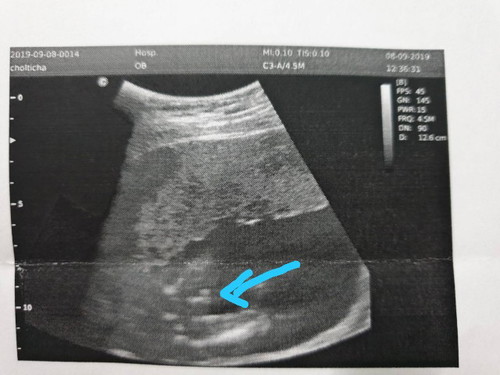

สอบถามค่ะ. คุณหมอบอกว่าผู้ชาย แต่ว่าเราดูไม่ค่อยออก แม่ๆคิดว่าผู้ชายผู้หญิงคะ

เค้าก็ว่าผู้ชายน้าาาา😄